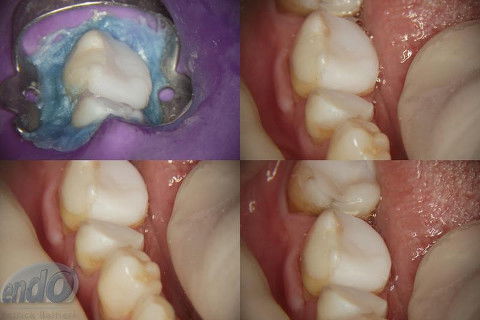

Os procedimentos pré-restauradores nos dentes 46 e 47 envolveram apenas a confecção de núcleo de preenchimento em resina composta (Z250 B0,5). No dente 45 foi instalado um pino de fibra de vidro (FGM) e confeccionado núcleo de preenchimento em resina composta (Z250 B0,5).

O prognóstico é favorável e a longevidade destes dentes depende dos procedimentos restauradores que serão realizados na sequência do tratamento.